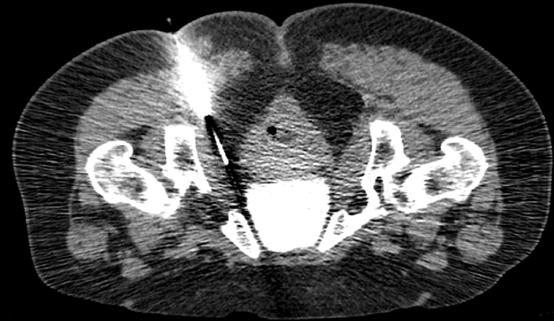

![]() 圖二:插入冷凍探針